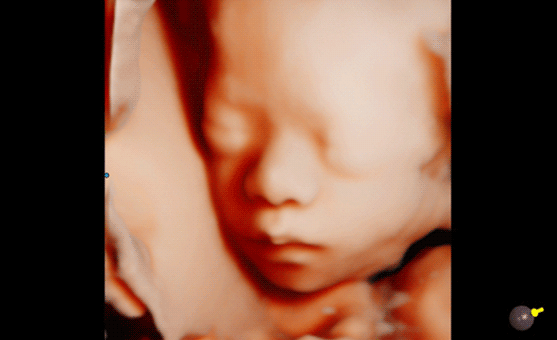

Le RealisticVue™ propose des rendus anatomiques de haute résolution en 3D/4D. Une source lumineuse est modélisée afin de permettre un effet d'ombre sur les structures et de surligner les zones d'intérêt.